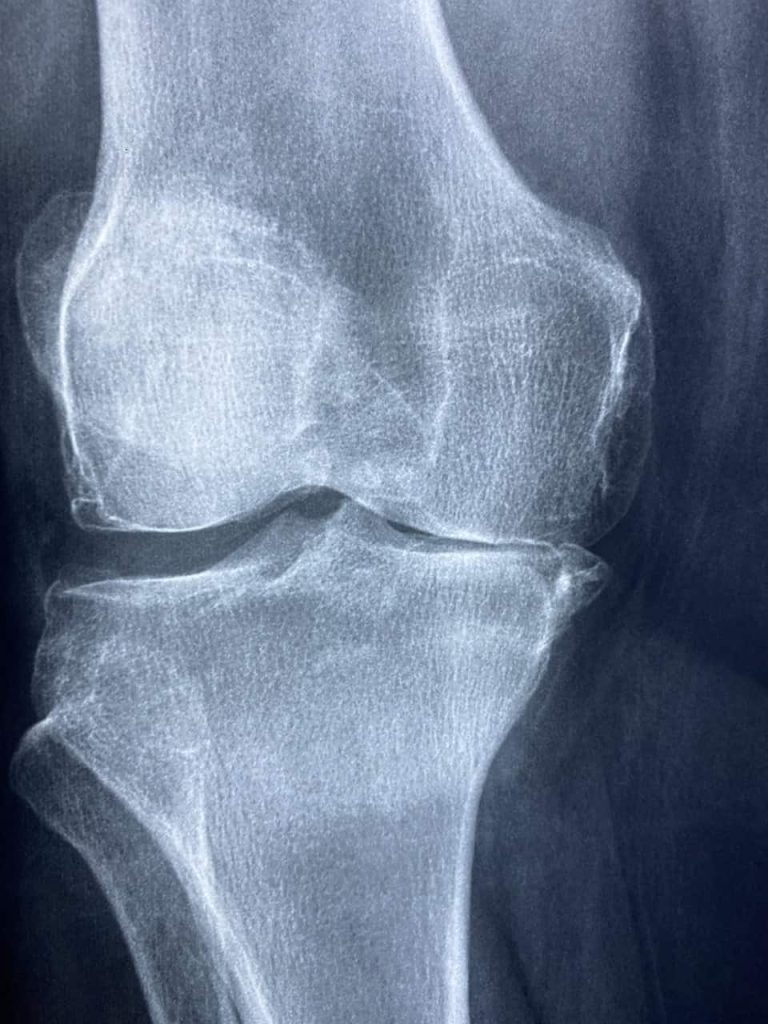

Moet ik een röntgenfoto van mijn knie laten maken?

Het maken van een röntgenfoto is in de meeste gevallen niet nodig om de diagnose knieartrose te stellen.